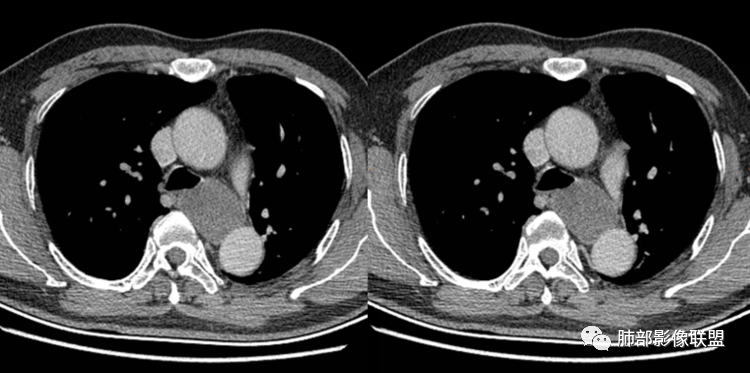

患者,男,43岁,无意间发现纵隔肿物,无胸闷胸痛,无心慌气短,无咳嗽,无吞咽困难等不适。体检发现的,无症状。

气管、左主支气管后方,食道左侧囊性占位,壁薄且均匀、光滑。气管及左主支气管受压凹陷、变形。

食道也受压变形、移位。